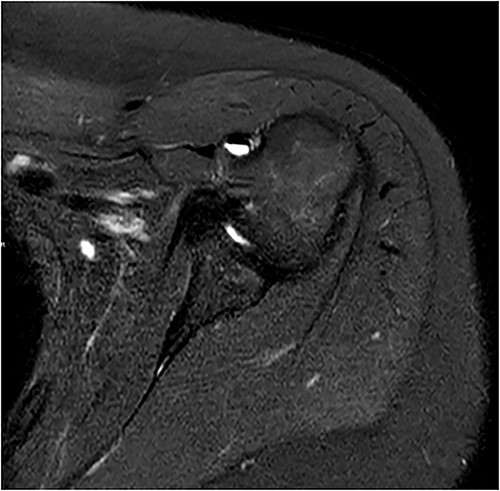

Standard anterior/posterior and lateral X-rays of the affected shoulder were done. The patient was diagnosed with adhesive capsulitis. She was therefore referred to office-based extensive rehabilitation program to improve range of motion and strengthen shoulder muscles. Though MRI does not play a rule in the diagnosis and management, we opted to do one, after consenting the patient, trying to understand the peculiarity of the case (Figs 1 and 2).

Coronal and axial T2 fat saturated image of left shoulder showing thickened inferior capsule of low T2 signal, characteristic of freezing phase in adhesive capsulitis.